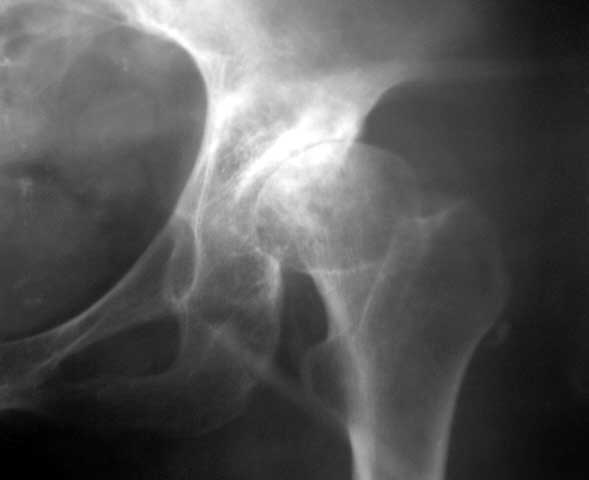

以下是引用yxfjnchina在2005-4-16 19:51:36的发言:[br]双侧髋臼稍浅平,髋臼外上缘可见骨质增生.左股骨头内密度不均,可见小囊状低密度影及不均匀硬化.小梁紊乱.考虑双侧髋臼发育不良并退行性骨关节病.左股骨头缺血性坏死待排

以下是引用dgma在2005-7-1 21:34:00的发言:[br][br]双侧髋臼发育不良。[br]退行性骨关节病。[br]左股骨头缺血性坏死?[br]建议:左股骨头mr扫描。